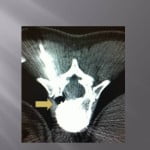

In case of lytic tumoral lesion invading the posterior wall.

The major risk is compression of the spinal roots by the cement. An excellent radio-opacity of the cement is fundamental to perfectly limit its position and its diffusion under continuous scopic control.

We position the trocar at the level of the most anterior portion of the tumor and cross the adjacent bone. We slowly inject a few drops of cement at the level of the vertebrae not invaded, then as the cement is getting more dense, we withdraw while injecting cement.

The lesion must be filled as much as possible. An bilateral entrance way can be very useful for an optimal filling. In case of a pedicular contact, the withdrawal of the trocar is performed slowly while injecting the rest of the very thick cement little by little to create a bone bridge under scopic guidance. The risk to reach nervous root is important by extension in the foramen, a perfect control of the move s compulsory to avoid nervous complications.